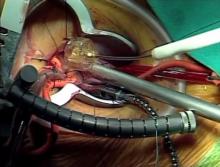

Mattia Glauber of Instituto Clinico Sant Amgrogio, Milan, Italy, argues in favor of the right anterior mini-thoracotomy approach for minimally invasive aortic valve replacement. Dr. Glauber uses a short video to illustrate the technique of sutureless valve insertion.